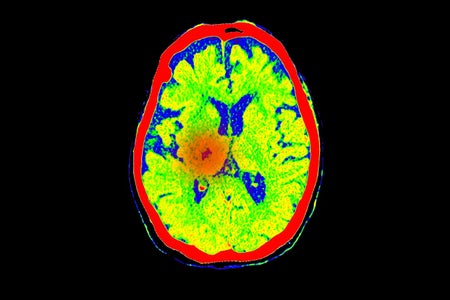

1 in 4 Unresponsive People with Brain Injuries May Be Conscious

More people than we thought who are in comas or similar states can hear what is happening around them, a study shows